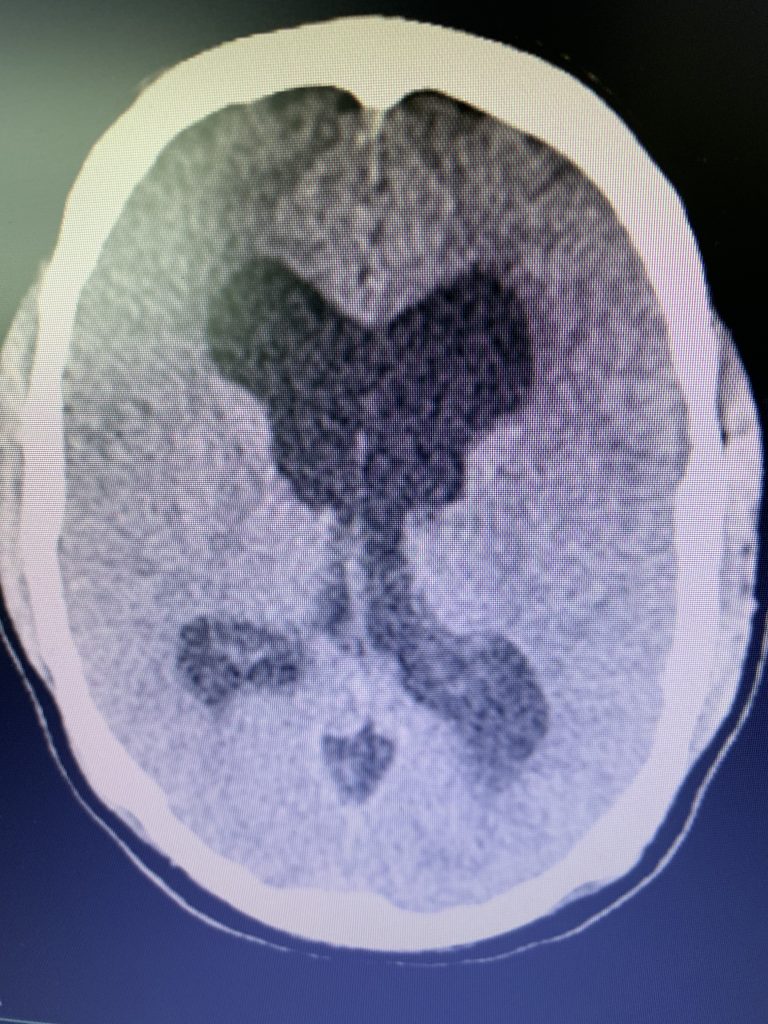

Figure 1B,C: Pre-operative CT images.

Prior to shunting, a head CT was obtained and the head CT in addition to documenting a patten of obstructive hydrocephalus suggested a possible mass lesion compressing the aqueduct at its inferior aspect. Figure #1 demonstrates the hydrocephalus and the possible lesion. A decision was made at this point that the patient had obstructive hydrocephalus that was now symptomatic and he was taken for a laparoscopic-assisted ventriculoperitoneal shunt.

On initial examination, the patient was neurologically intact without complaints of headache. His imaging; however, did show hydrocephalus, most notably the lateral and third ventricles with a normal sized fourth ventricle. Given that the patient had no complaints, a decision was made to follow this expectantly and he was referred for a neuro-ophthalmologic evaluation, which confirmed no evidence of papilledema. MRI was otherwise negative.